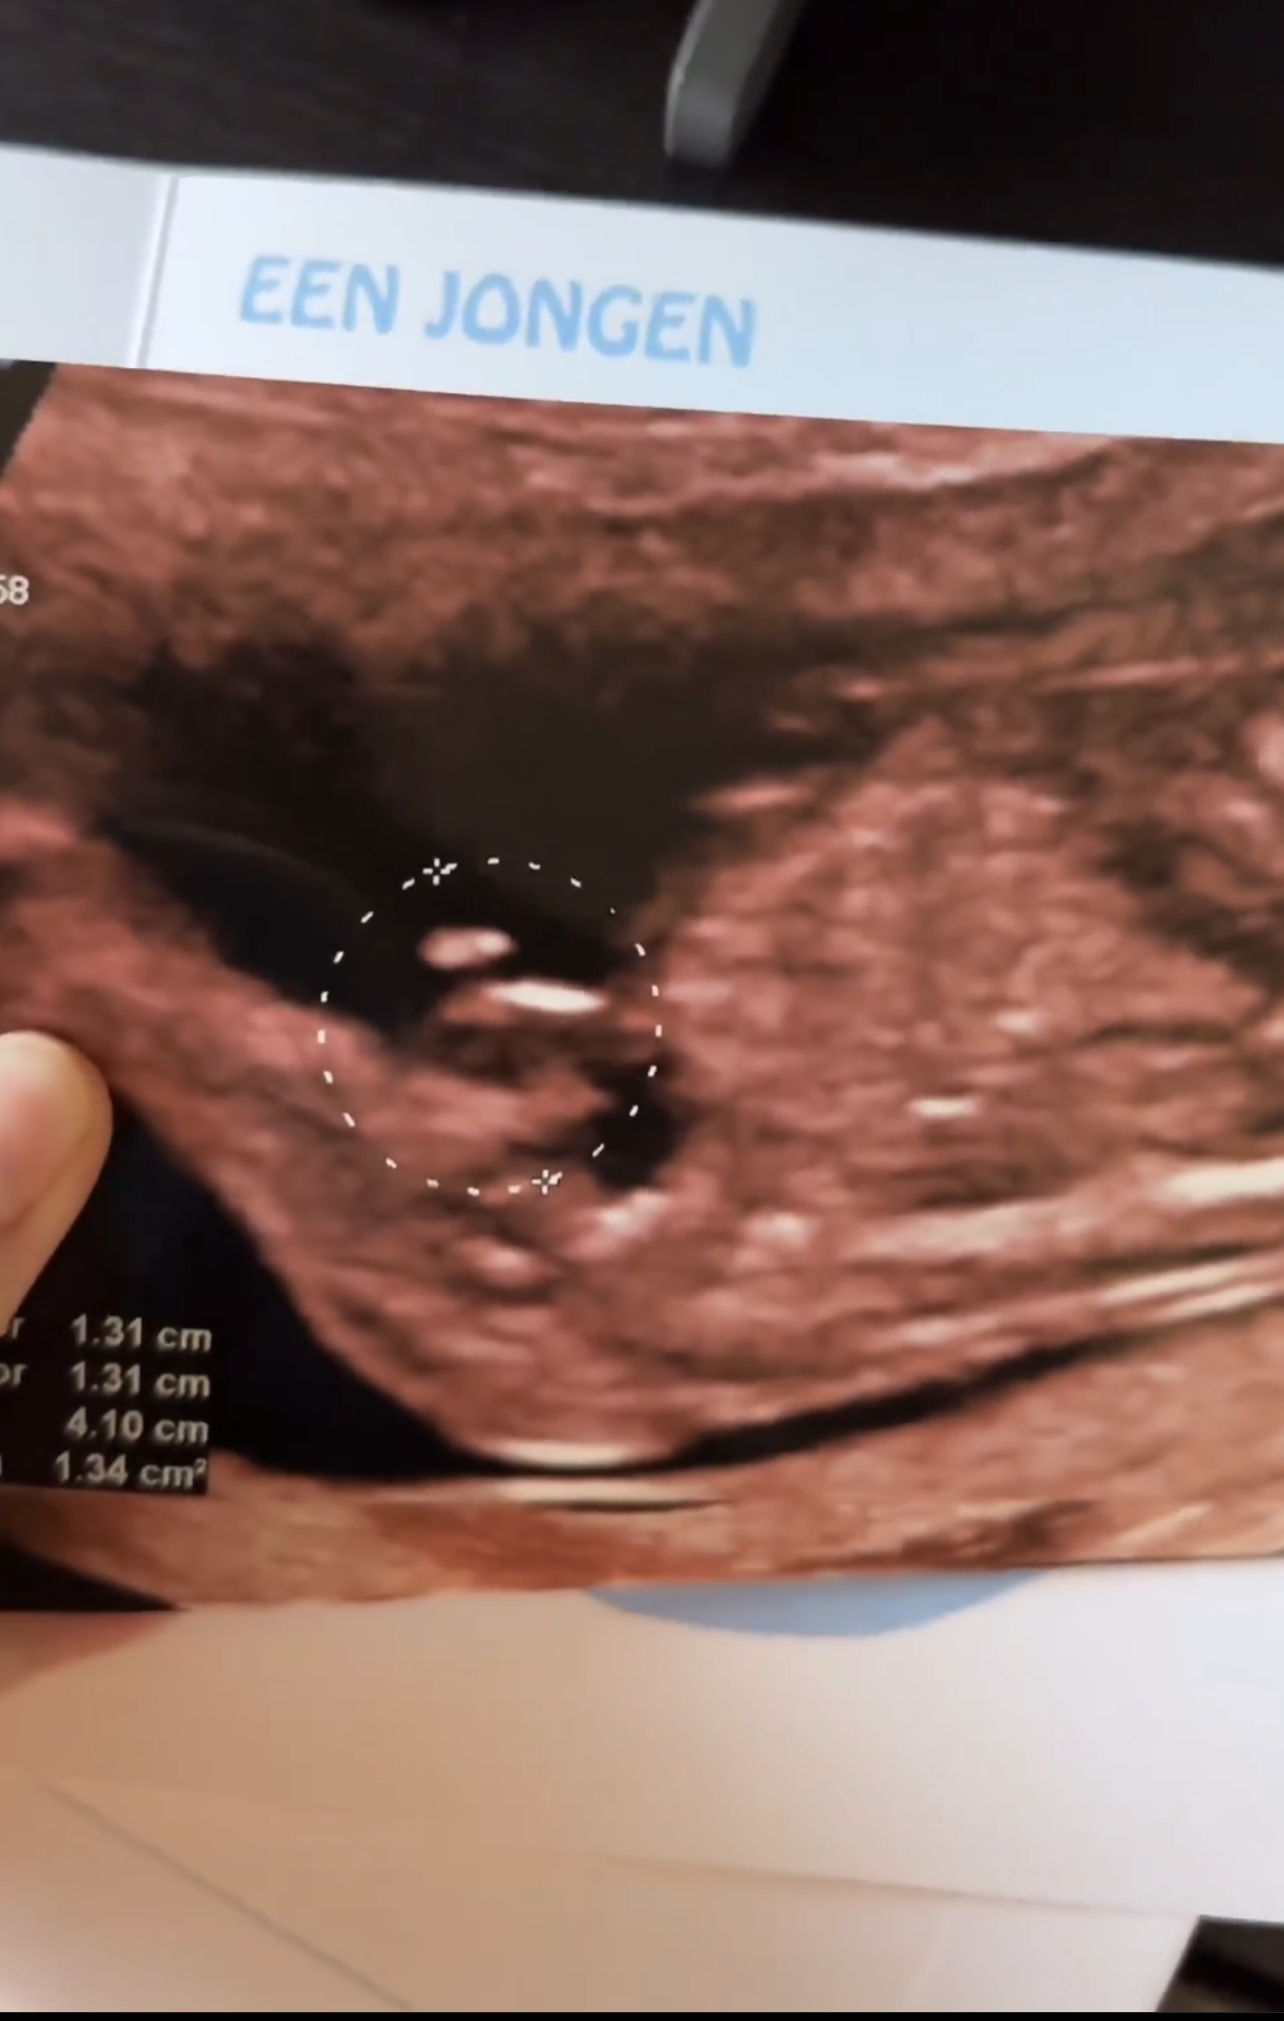

Gender Reveal: Een Jongen!

Sesuai prediksi mak2 disini ya holcim 2.0 berjenis kelamin cwk 👶🏻